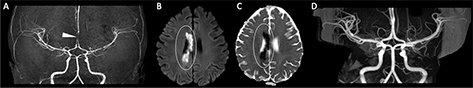

Fig 5

Figure 5. A 13-year-old previously healthy female who presented with new left-sided facial weakness. Diffusion weighted image (A) demonstrate acute infarcts in the right middle cerebral artery (MCA) territory (black arrows). Time-of-Flight MRA (B) shows stenosis of the proximal right M1 MCA segment (white arrowhead). Vessel wall imaging (C) demonstrates a cuff of enhancement at the stenosis (white arrow). Digital subtraction angiography (D) demonstrates a focal arterial irregularity and banding (black arrowhead) resulting in mild stenosis, compatible with focal arteriopathy of a likely inflammatory nature.